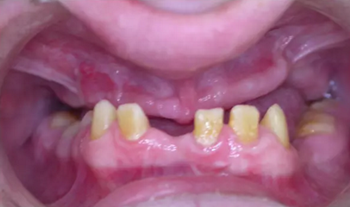

該患者 12 歲時(shí)已診斷為釉質(zhì)發(fā)育不全。家族史正常,否認(rèn)全身系統(tǒng)性疾病。全身系統(tǒng)檢查無明顯異常,檢查雙側(cè)顳下頜關(guān)節(jié)、開口度正常??趦?nèi)及 X 片檢查見上頜縮窄,上頜牙列缺失,安氏三類錯(cuò)牙合,下頜牙牙冠短小,牙根正常。上頜大量牙槽骨因以前手術(shù)干預(yù)而喪失,后牙區(qū)牙槽骨高于前牙區(qū)。病變牙齒在之前的治療中已被拔除。

圖 4. 術(shù)前口內(nèi)照